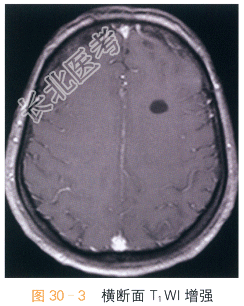

女,28岁,头痛、头晕4月余。

读片分析:头颅横断面T₁WI,T₂WI显示左侧额叶均匀的长T₁WI,长T₂WI信号,边界清晰,周围脑实质未见水肿;横断面、矢状面T₁W增强显示左侧额叶病灶未见明显强化。结合病史,患者考虑为神经上皮囊肿。